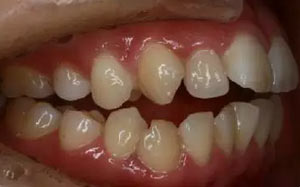

—上中線左偏,下中線右偏

—咬合平面右低左高

—前牙開(kāi)合

—右側(cè)磨牙近中關(guān)系,尖牙遠(yuǎn)中關(guān)系

—左側(cè)磨牙遠(yuǎn)中關(guān)系,尖牙近中關(guān)系

—前磨牙區(qū)及前牙區(qū)均為開(kāi)合

—右側(cè)自第一磨牙開(kāi)始至側(cè)切牙均為反合

上牙弓:尖圓形,25腭側(cè)完全錯(cuò)位,26前移

下牙弓:卵圓形,下前牙區(qū)擁擠